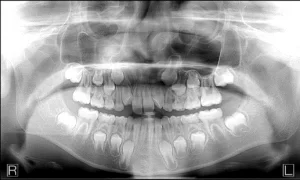

There is a growing desire by health care facilities to add panoramic dental x-ray modalities to their capabilities.  The main reasons for this are a combination of the panoramic x-ray’s broad diagnostic capabilities along with it’s low cost and low radiation relative to other traditional medical imaging modalities.  Here are three common applications:

1.  Emergency rooms and urgent care facilities value the targeted anatomy and field of view as be an ideal modality to assess facial trauma.   For example, as more of these facilities are seeing patients with severe or emergency dental ailments, the staff values the panoramic dental modalities to help determine whether the patient should be referred to a dentist or to another specialist.